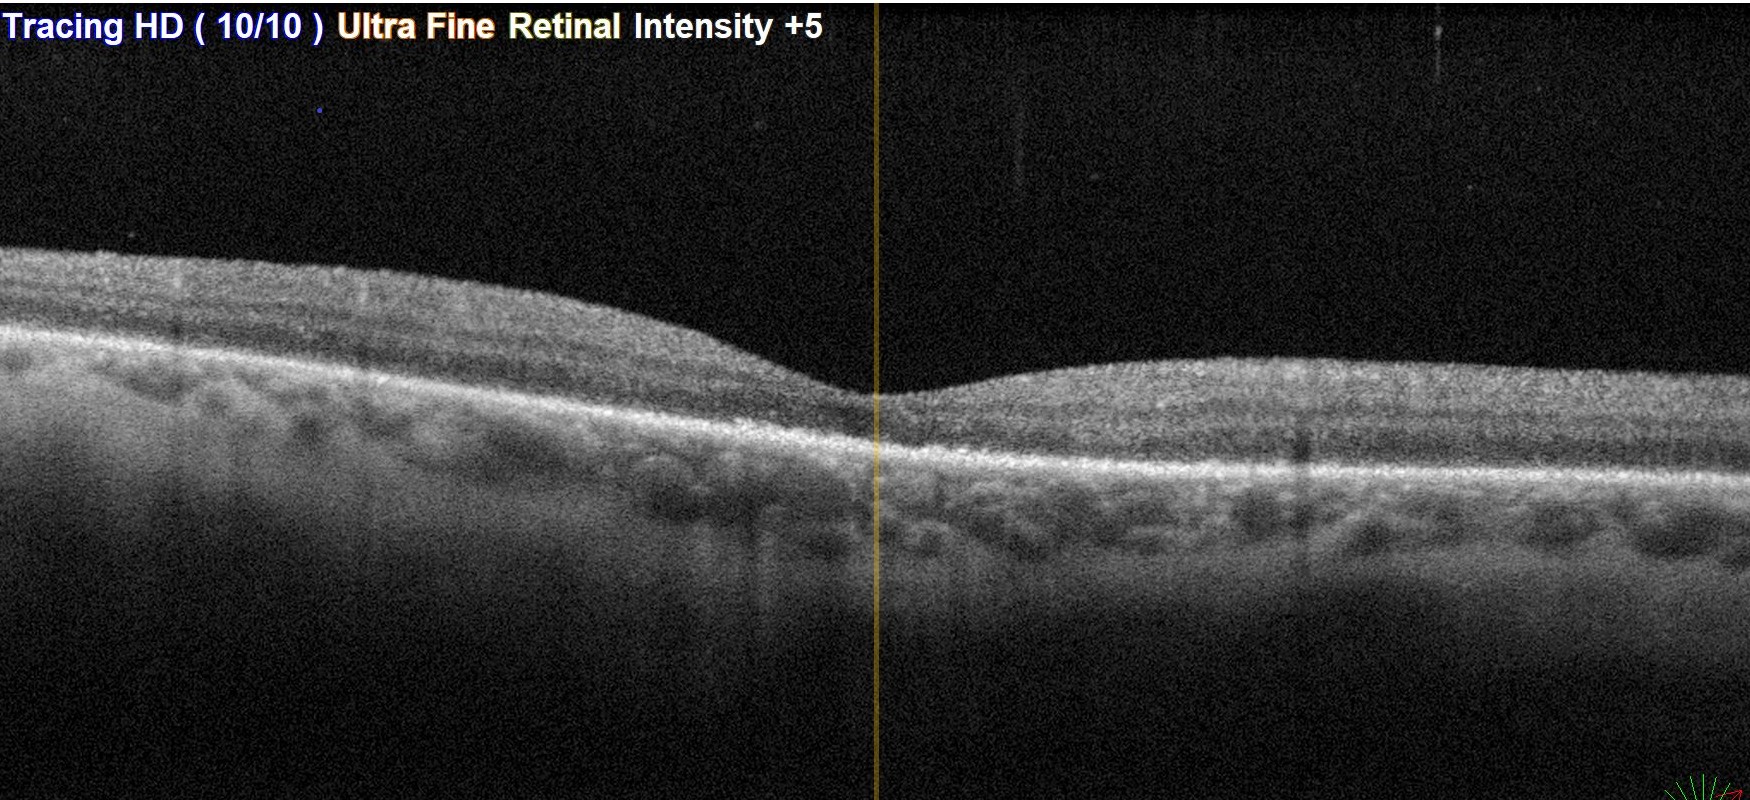

Sağ gözde büyük at nalı yırtığa bağlı gelişmiş olan büllöz retina dekolmanı.Ameliyat öncesi, pars plana vitrektomi ve gaz injeksiyonundan 2 ay sonraki geniş açılı gözdibi görüntülemesi ve ameliyat sonrası maküladan alınan OCT kesiti.